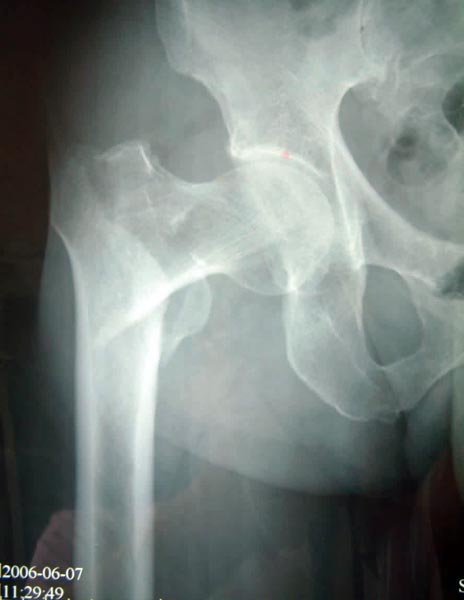

患者82岁,男性,股骨粗隆间粉碎骨折,伴有冠心病、骨质疏松。

采用小切口微创双极人工股骨头置换术置换术,骨折块用钢丝固定。